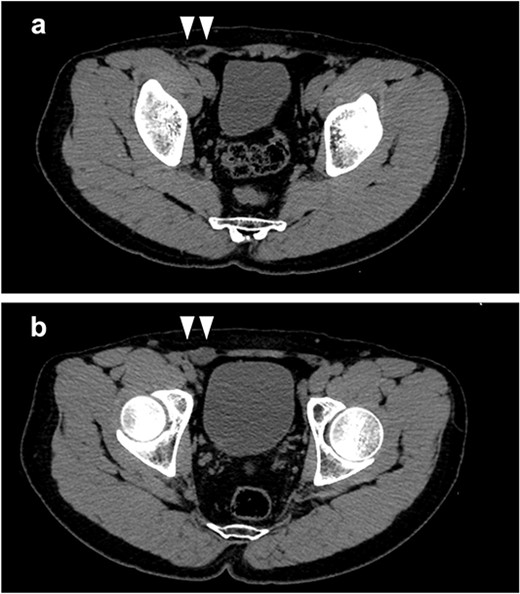

CT examination revealed an indirect inguinal hernia and protrusion of intra-abdominal fat (Fig. 1a). Based on these findings, the patient was diagnosed with a right inguinal hernia and was scheduled to undergo a laparoscopic hernia repair (TAPP). Intraoperative observation revealed a 30-mm white mass in the dorsal part of the hernia orifice (Fig. 2). Intraoperative physical examination of the patient revealed that the right testicle was not palpable, and the patient was diagnosed with intraperitoneal testis. The hernia was an indirect hernia ~2 cm in diameter at the hernia orifice. A review of the CT scan revealed a slightly hyperabsorbable mass near the internal inguinal ring, which was thought to be a right cryptorchidism (Fig. 1b). Since there were no relatives of the patient who could give consent for the surgery in Japan, the surgery was suspended. We explained the need for the orchiectomy to the patient and obtained his consent for the surgery. Simultaneous TAPP and laparoscopic orchiectomy were planned at a later date. Under general anesthesia, the operation was performed with three ports: one 12-mm port umbilical and two 5-mm ports bilateral abdominal. Bird® 3D Max L size mesh was used for the right port. The right testicle was removed from the umbilical port wound using an extraction bag after clipping the deferent duct, testicular vessels, and gubernaculum testis (Fig. 3a–c). The operation time was 150 minutes, and the blood loss was 0 ml.

(a) Intra-abdominal fat was found to be prolapsed from the lateral side of the inferior epigastric vessels; (b) a low-density mass (white arrows) in the cranial side of the internal inguinal ring was detected, which was considered to be an intraperitoneal testis.